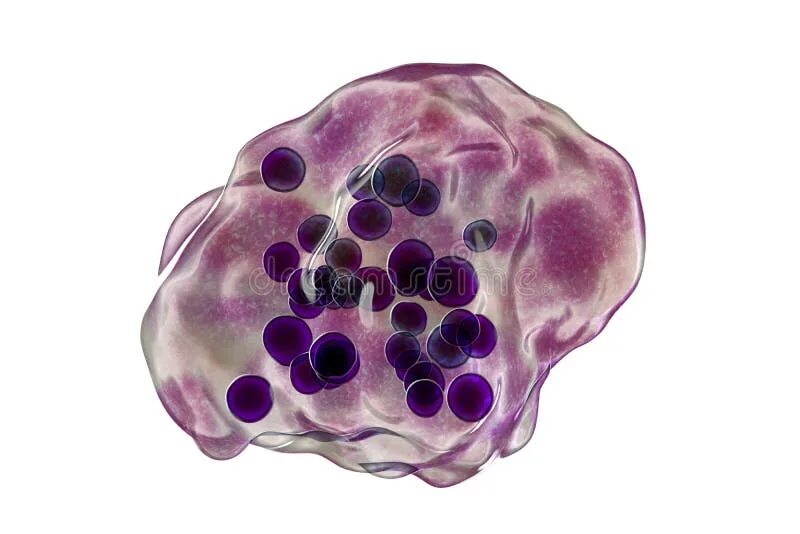

Клетка типа инородных тел